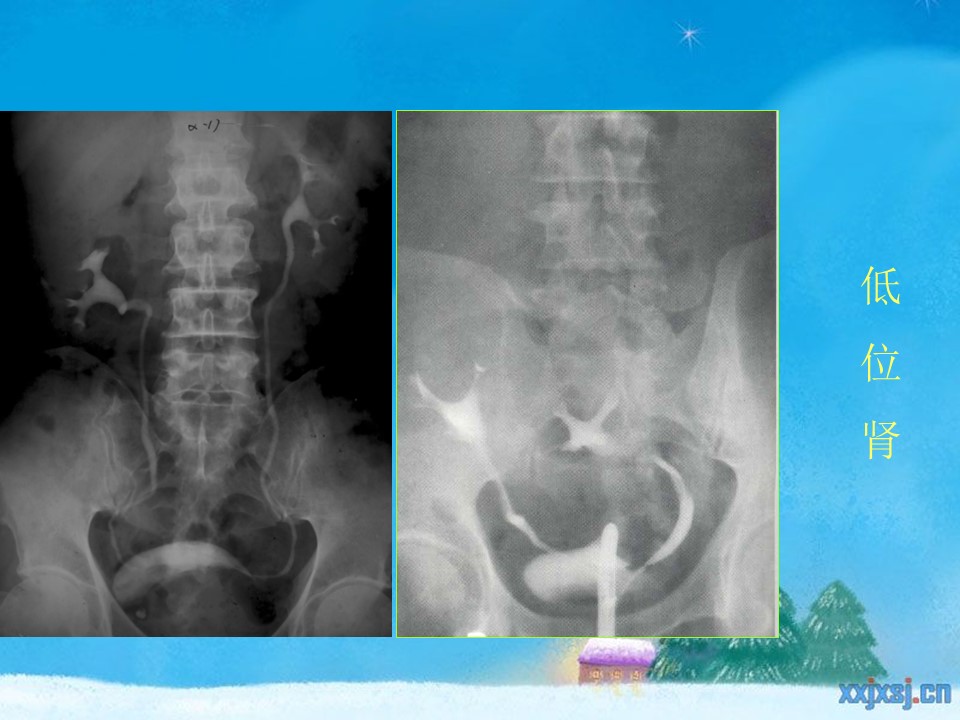

“腹部、盆腔影像诊断学PPT” 的相关文章